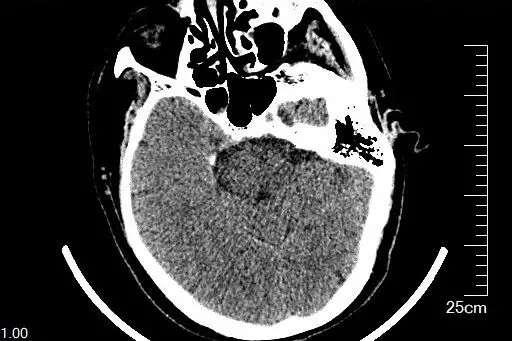

辅助检查中,心电图未见明显异常,头颅 CT 提示右侧侧脑室后角旁缺血灶可能(与本次疾病无关,余未见其它病灶排除继发性周围性面瘫),结合临床表现及体征,患者主要症状符合左侧周围性面神经受损特征